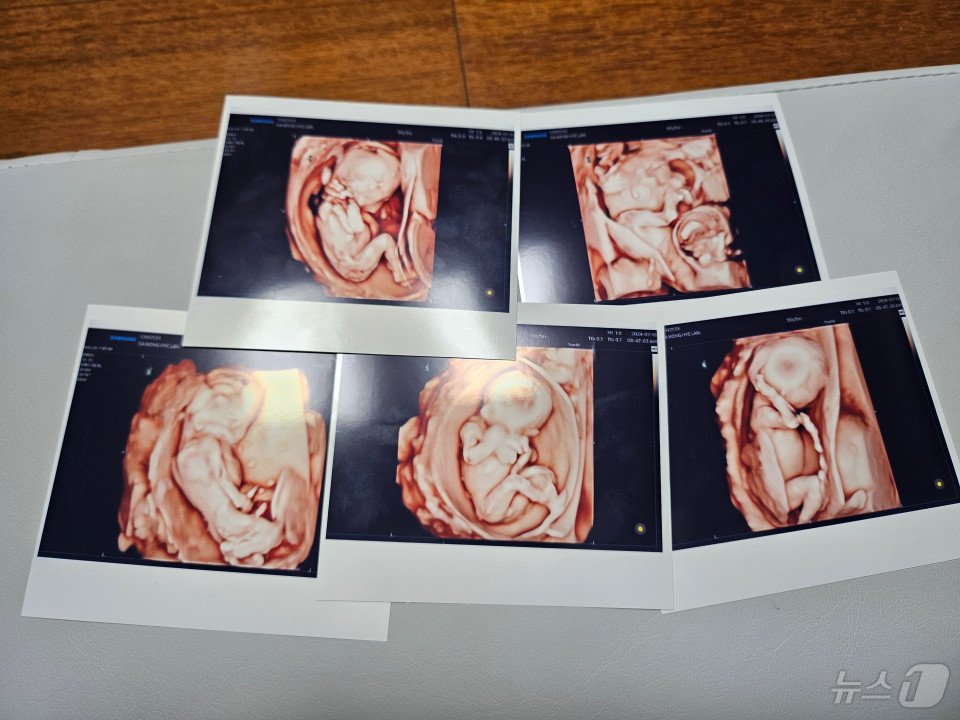

20일 서울성모병원에서 다섯 쌍둥이가 탄생했다. 사진은 오둥이의 초음파 사진. (병원 제공)

30대 산모가 자연임신으로 얻은 다섯 쌍둥이를 분만했다. 다섯 쌍둥이 출산은 세계적으로도 드문 사례인데 자연임신으로 생긴 다섯 쌍둥이가 탄생한 건 국내 첫 사례다.

가톨릭대학교 서울성모병원은 산부인과 홍수빈·소아청소년과 윤영아·신정민 교수팀이 30대 산모의 다섯 신생아 다태아 분만을 성공리에 마쳤다고 20일 밝혔다.